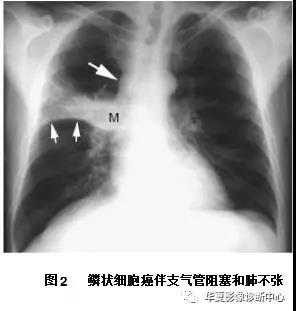

影像学表现常见息肉状腔内肿块和(或)支气管阻塞(图1A)。肺门的肿块也很常见,这归因于肿瘤位于中心位置,可侵犯局部组织,累及肺门淋巴结(图1B)。肺不张(图2)实变、黏液嵌塞和支气管扩张常见,提示支气管阻塞。只有30%的鳞癌表现为肺外围结节。中央坏死和空洞(图3)较其他类型肺癌更常见。

胸片显示右肺门大肿块(M) 伴水平裂向上弯曲移位( 小箭头)。呈反“S”征,可见纵隔淋巴结增大( 大箭头)